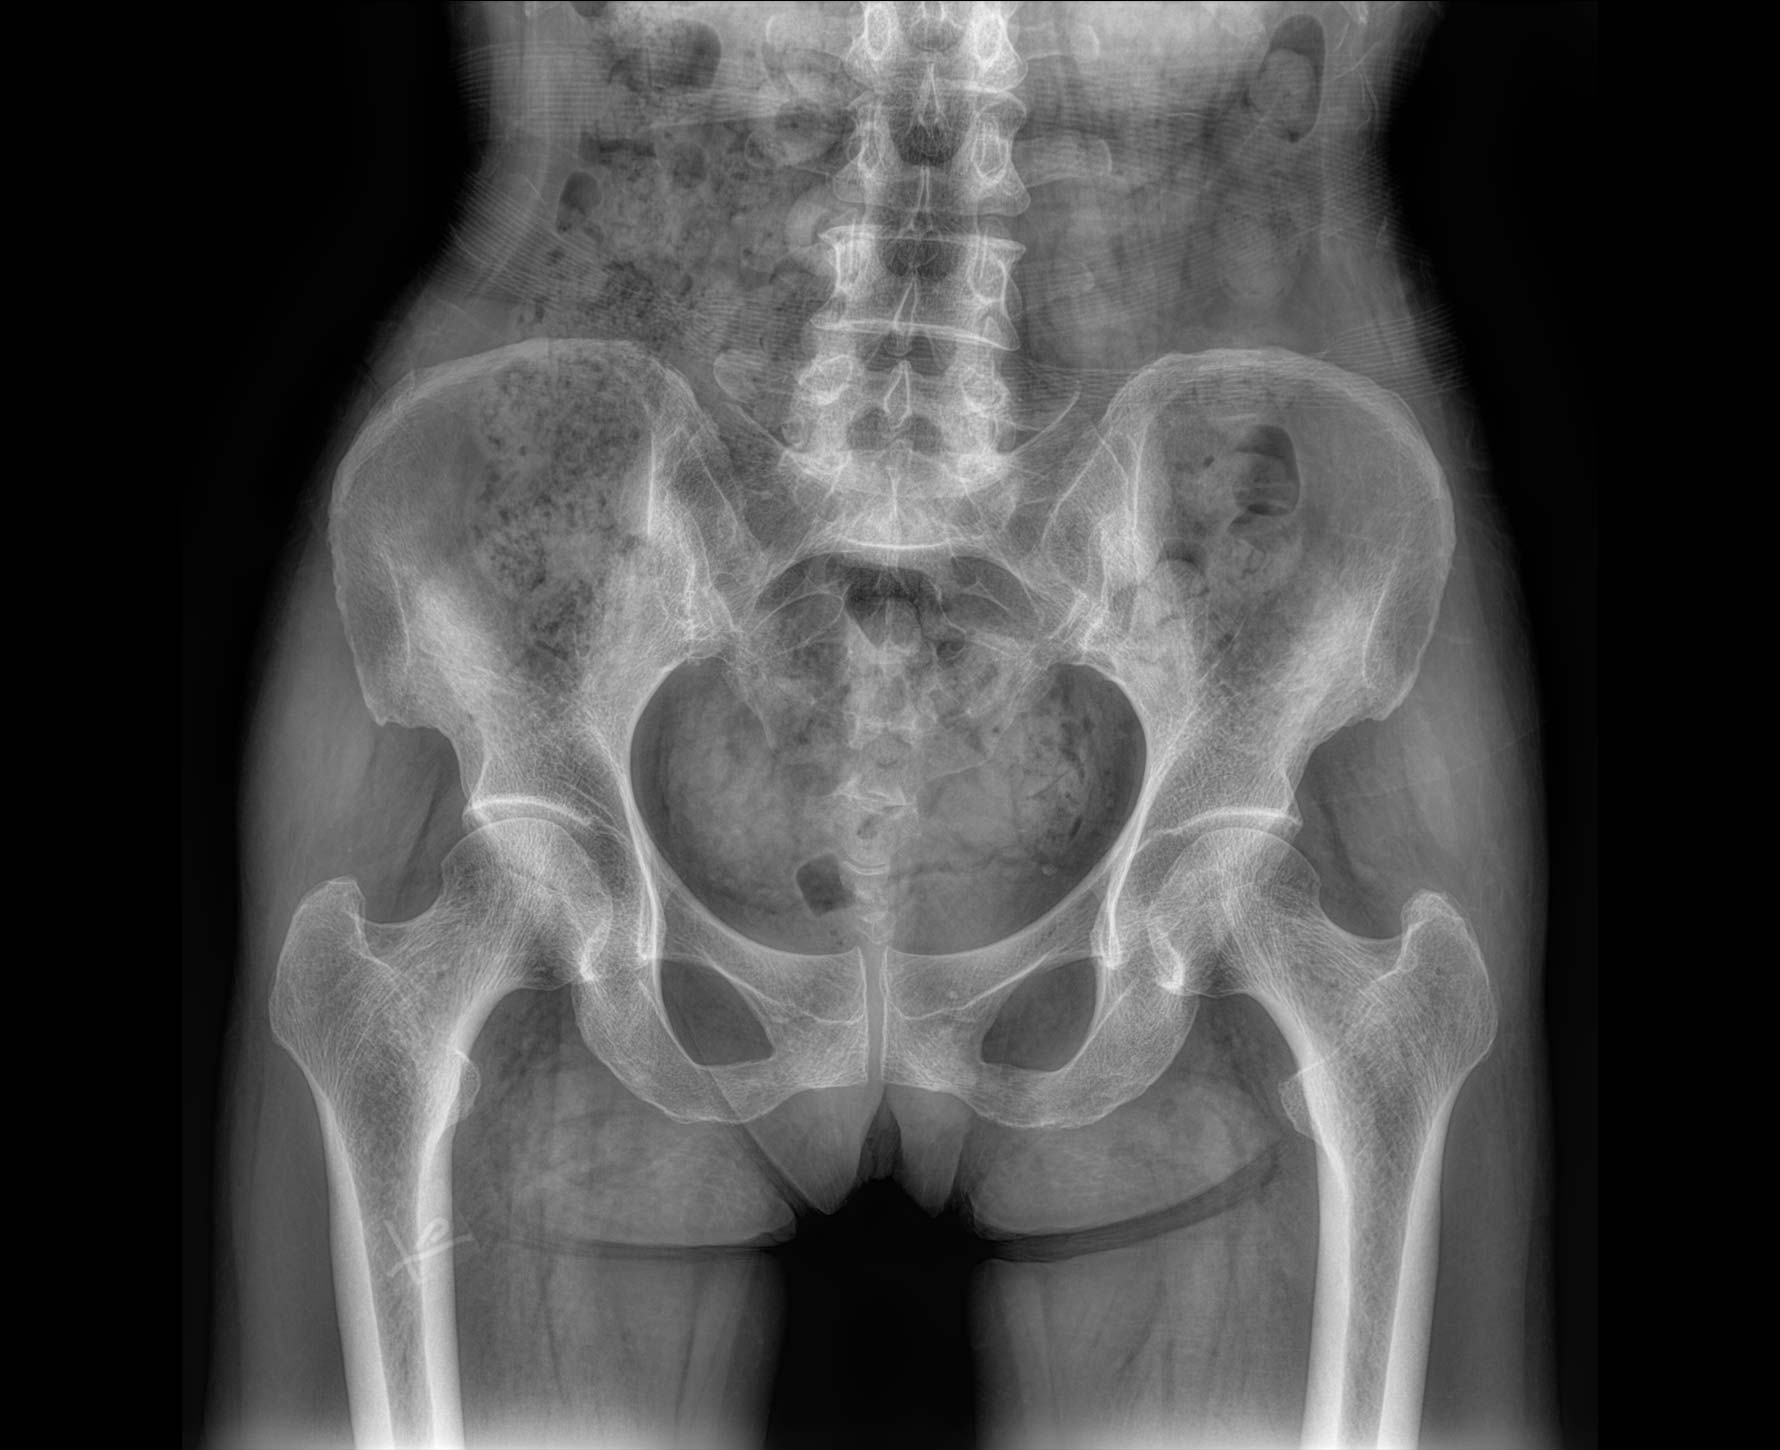

临床图像